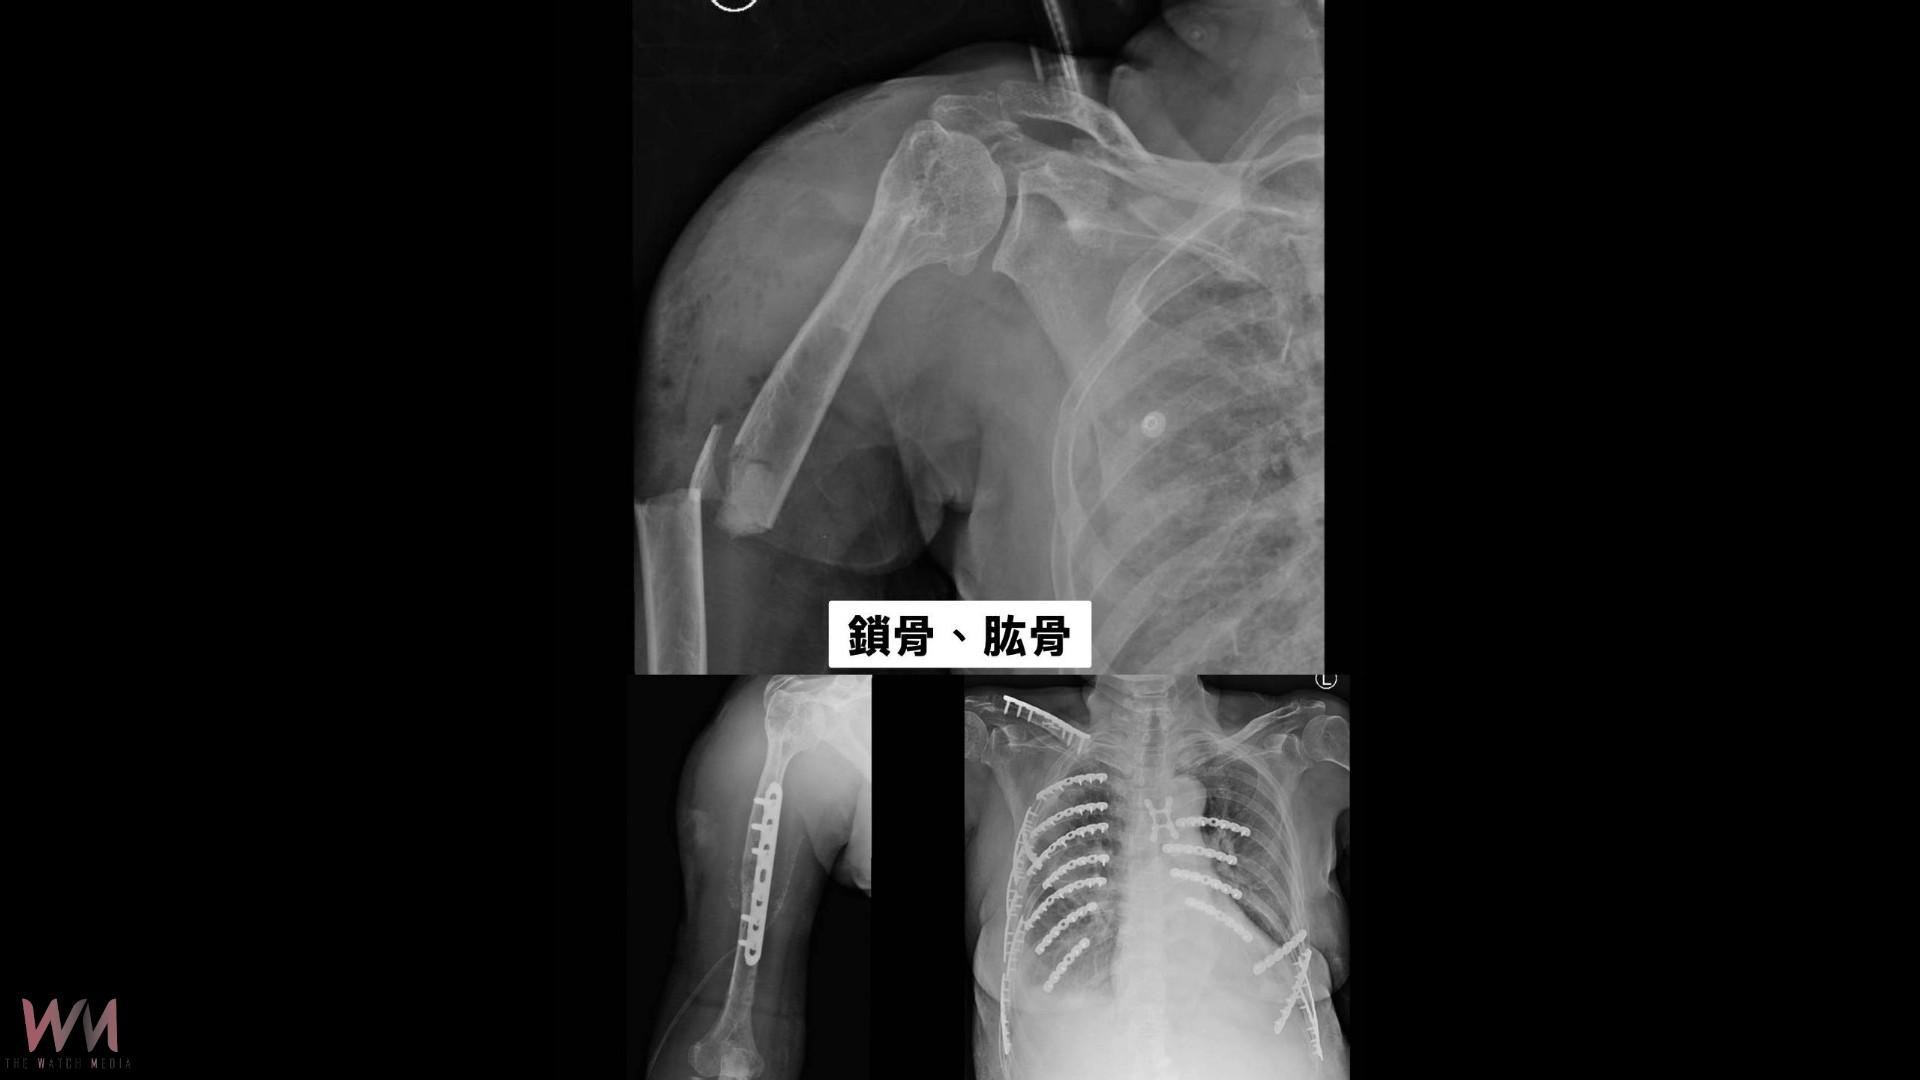

送抵急診時,黃婦遍體鱗傷,右上臂開放性骨折、右側血胸,鎖骨、肱骨、橈骨、骨盆、脛骨、腓骨等多處骨折,連胸椎第6至9節及胸骨都受損。由於出血量大、血壓持續下降,醫院立即啟動創傷小組,全力急救。

彰化醫院胸腔外科主任林聿騰指出,病人肋骨21處骨折、胸廓變形、氣胸及血胸,形成嚴重的「連枷胸」,呼吸困難且併發肺炎風險高。準備進行開胸手術時,卻又出現延遲性小腸破裂,必須先由外科緊急切除部分小腸,再回到胸腔手術,可說一波未平、一波又起。

林聿騰說,醫療團隊利用3D影像重建胸廓,以微創方式植入鈦合金骨板與骨釘固定肋骨,穩定胸腔結構,讓她能重新呼吸。之後再由骨科接手進行四肢與骨盆的修復手術。